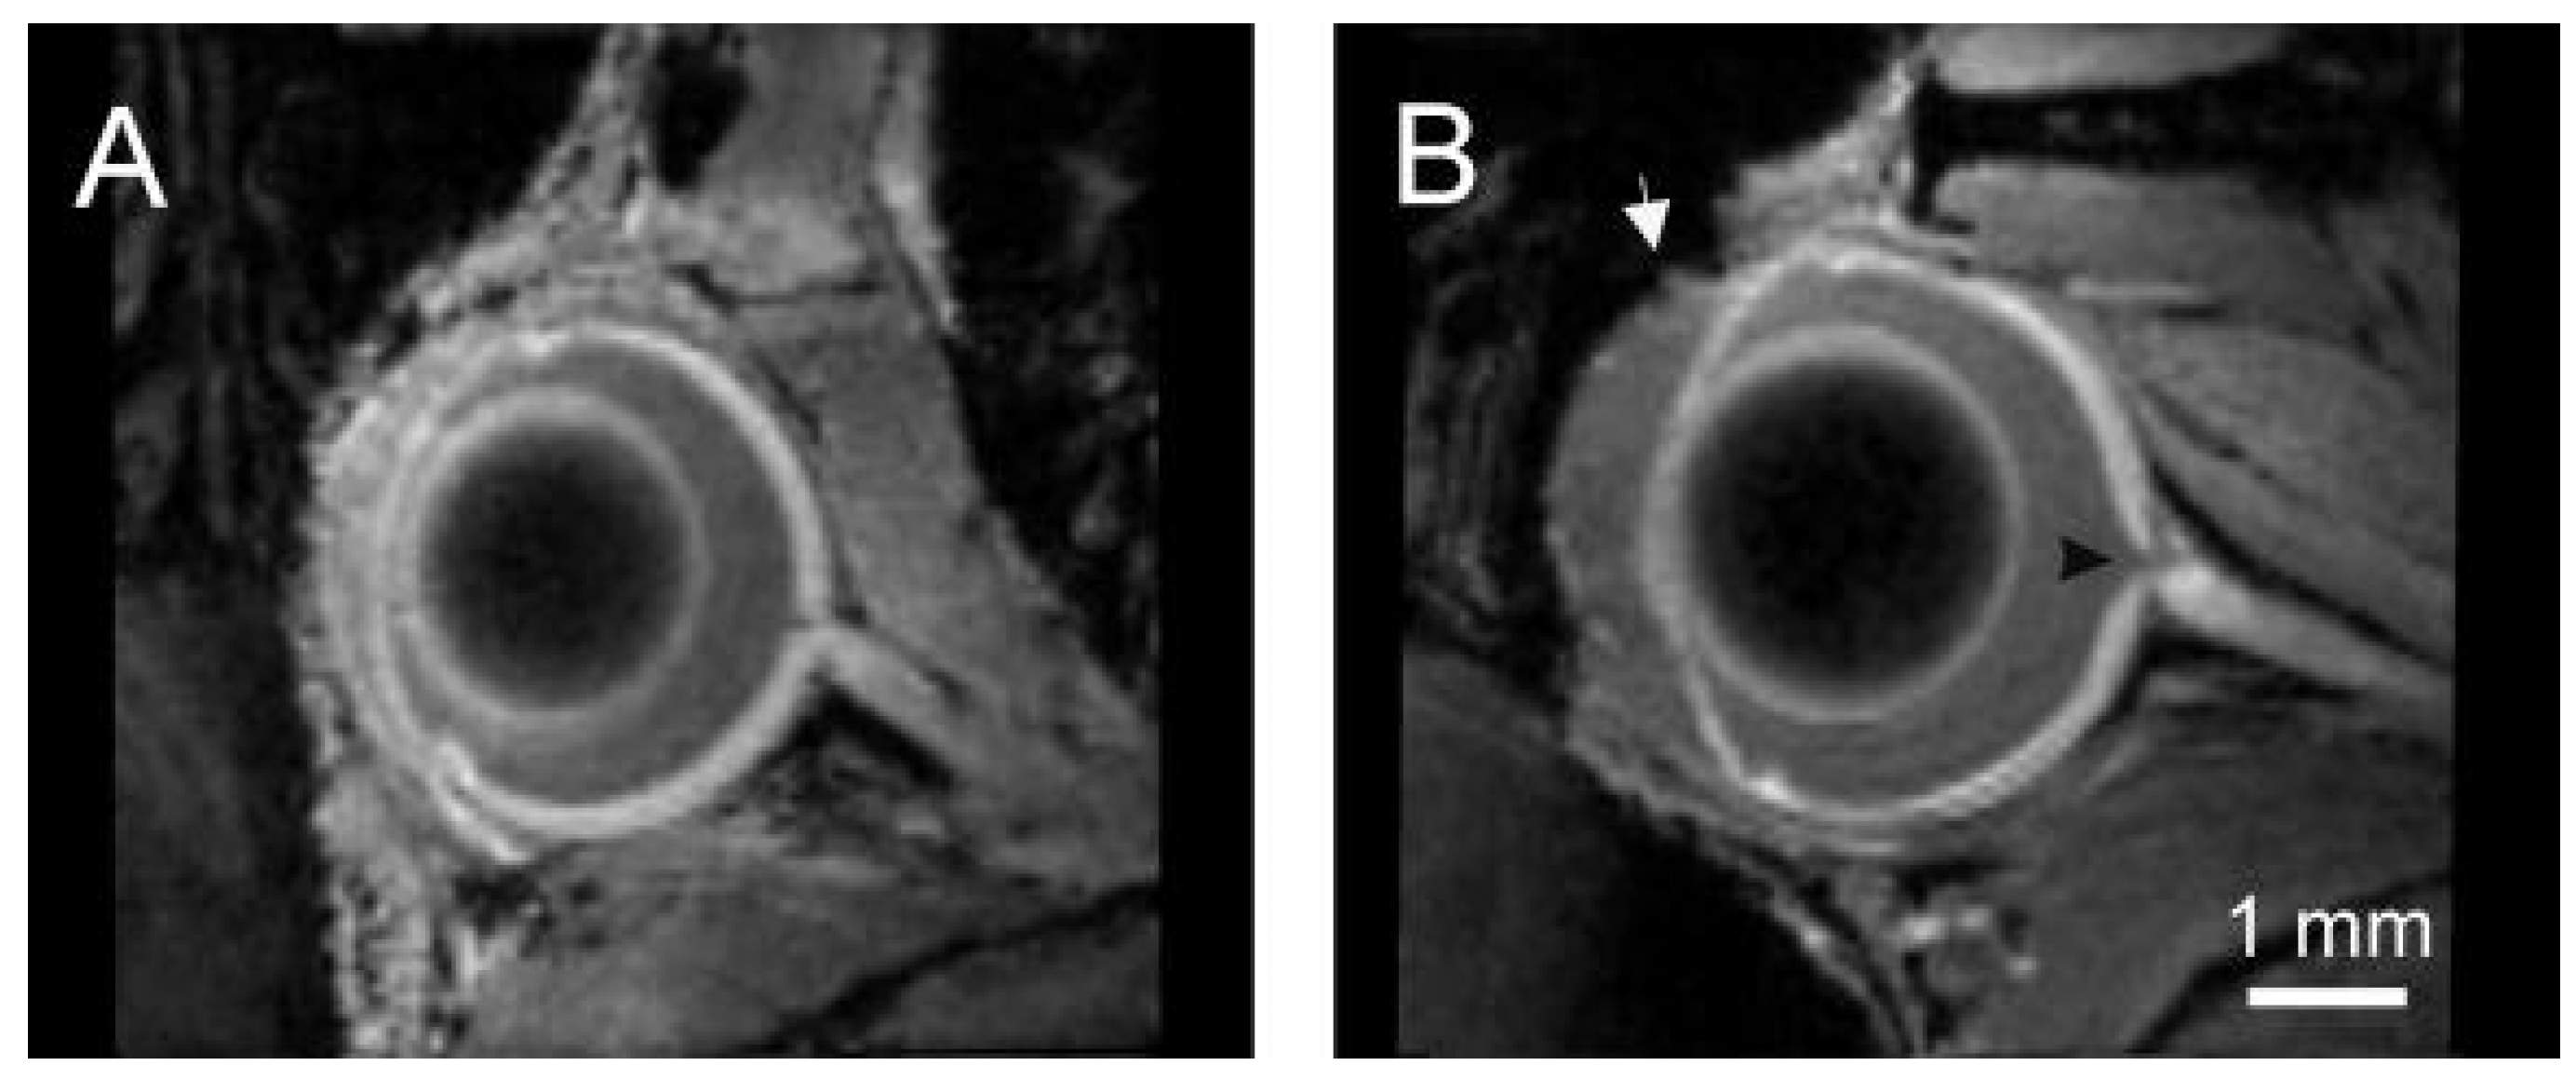

- Crosbie, D.E.; Keaney, J.; Tam, L.C.S.; Stamer, W.D.; Campbell, M.; Humphries, P. Age-related changes in eye morphology and aqueous humor dynamics in DBA/2J mice using contrast-enhanced ocular MRI. Magn. Reson. Imaging 2019, 59, 10–16. [Google Scholar] [CrossRef]

- Fiedorowicz, M.; Wełniak-Kamińska, M.; Świątkiewicz, M.; Orzeł, J.; Chorągiewicz, T.; Toro, M.D.; Rejdak, R.; Bogorodzki, P.; Grieb, P. Changes of ocular dimensions as a marker of disease progression in a murine model of pigmentary glaucoma. Front. Pharmacol. 2020, 11. [Google Scholar] [CrossRef]